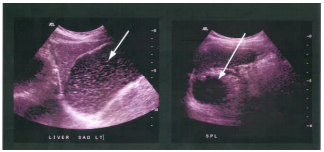

47 附圖中箭號所指的構造為何?

(A) 門靜脈(portal vein) (B) 總膽管(common bile duct)(C) 下腔靜脈(inferior vena cava) (D) 上腸繫膜靜脈(superior mesenteric artery)

61 所附之超音波掃描圖係來自同一受檢者,左圖為左上腹的縱向切面掃描,右圖為左上腹冠狀面掃描, 箭號所指的同一個器官為:(A) 脾臟(B) 腎上腺(C) 大腸(D) 胃